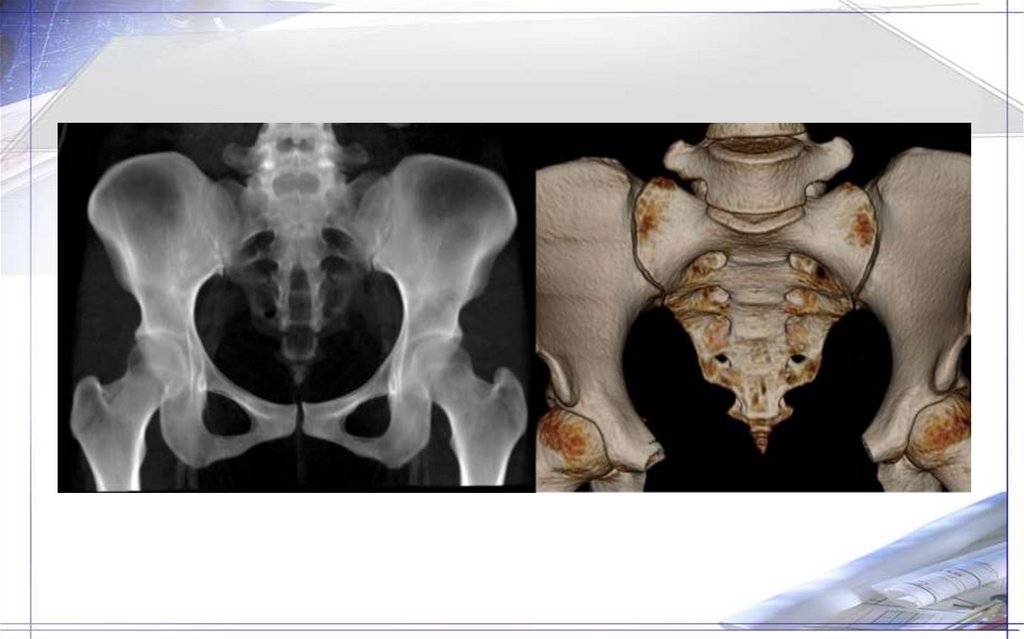

27. Крестец (os sacrum) и копчик (os coccygis)